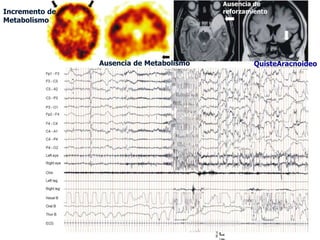

Ausencia de

Incremento de                             reforzamiento

Metabolismo

Ausencia de Metabolismo            QuisteAracnoideo